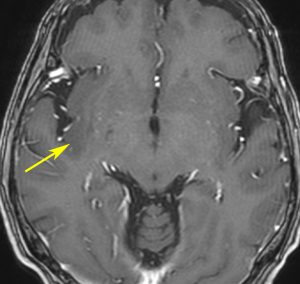

まずMRIで診断です

右側頭葉島の病変です。1年間の経過ではっきり増大したので,無症状でしたが生検術を行いました。病理組織では,異型グリアの増殖はありましたが,核分裂蔵,血管内皮の増生や壊死は明らかではありませんでした。しかし,遺伝子診断ではIDH1/2 野生型,ATRX retained,TERT promotor野生型,1p/19q共欠失なしでした。膠芽腫という確定病理診断です。

標準治療を加えましたが,数ヶ月後に急激な増大を呈しました。グレード4の臨床像です。MRI画像よりも病理組織像よりも,遺伝子診断の方がより性格に予後を示す例です。

診断:MRIでの特徴

• 診断はMRI検査をします,それだけで十分です

• ガドリニウム造影剤で腫瘍の周辺が白く造影されます

• いびつな形になるのが特徴です

• しかし,ほんとうの腫瘍の広がりは,T2強調あるいはFLAIR(フレア)という画像で,白く滲むように写る部分すべてです

典型的な膠芽腫のガドリニウム増強画像です。右の側頭葉から発生したために目立った症状が無く,この大きさで発症しました。何となくボッとしていると言うのが訴えでした。腫瘍の周囲がガドリニウムで白く増強されて,内部は壊死で低信号(黒っぽい)になっています。